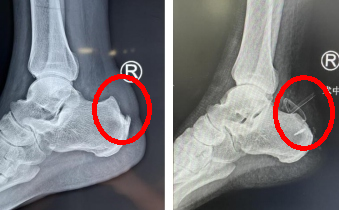

接诊的赵亮主治医师经过仔细查体及x光片检查,诊断孟师傅患有跟腱末端病、Haglund综合征,是由于Haglund畸形导致跟腱及周围滑囊病变,引起的足部后跟痛,早期可以选择保守治疗,但发展到孟师傅这种程度就需要手术干预了。

术前术后x光对比